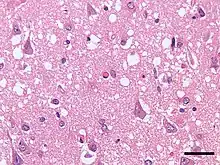

| Micrograph showing spongiform degeneration (vacuoles that appear as holes in tissue sections) in the cerebral cortex of a patient who had died of a prion disease (Creutzfeldt-Jakob disease). H&E stain. Scale bar = 30 microns (0.03 mm). | |

Prions cause neurodegenerative disease by aggregating extracellularly within the central nervous system to form plaques known as amyloids, which disrupt the normal tissue structure. This disruption is characterized by "holes" in the tissue with resultant spongy architecture due to the vacuole formation in the neurons.[68] Other histological changes include astrogliosis and the absence of an inflammatory reaction.[69] While the incubation period for prion diseases is relatively long (5 to 20 years), once symptoms appear the disease progresses rapidly, leading to brain damage and death.[70] Neurodegenerative symptoms can include convulsions, dementia, ataxia (balance and coordination dysfunction), and behavioural or personality changes.